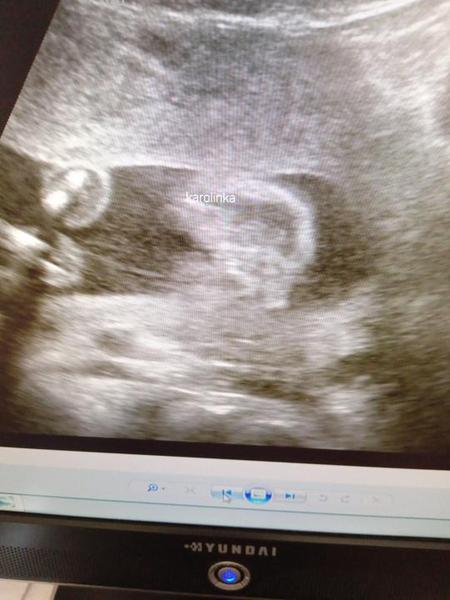

chtěla bych se s vámi poradit, co si myslíte, že čekáme 🙂, určitě máte některé zkušenější oko než my a jelikož jsme od doktorů slyšely obě varianty, ráda se poradím i s vámi, určitě jste takových obrázků už viděly spoustu 🙂. Přikládám foto z UTZ ve 20.týdnu. Moc děkuji!

Holky moc děkuji za reakce 🙂. Mně se to také spíše zdá jako holčička, pan doktor nám ale právě během této kontroly řekl, že tam vidí spíše kluka, což mě dost překvapilo 😃. Je mi jasné, že jistotu budeme mít až po porodu, ale spíš jsme prostě zvědaví 🙂.

Mně to zase přijde víc jako kluk, vpravo je tam něco jako pytlík vedle toho kávového zrna... No těžko říci 😀

Holčička😊 krásná buchta tam je